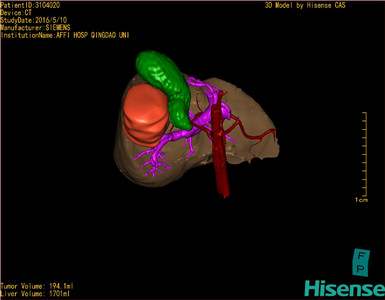

将0.625mm双源薄层CT资料的静脉期和动脉期Dicom格式文件导入海信CAS系统。

通过调节窗宽窗位调整CT序号,对肿瘤,肝实质,胆囊,下腔静脉,肿瘤,肝动脉、门静脉及肝静脉等进行三维重建;系统自动计算肿瘤体积和肝脏体积。

模拟手术操作,自动计算切除肿瘤体积。肝脏体积为1701ml,肿瘤体积为194.1ml,肿瘤体积为肝脏体积的11.4%,通过比对60-70岁正常肝脏体积为1262.7±284.31 ml,通过术前模拟手术,精准判断切除后剩余肝脏体积能耐受,避免肝衰竭发生。

术前手术方案的规划。

术前三维重建:

重建图片